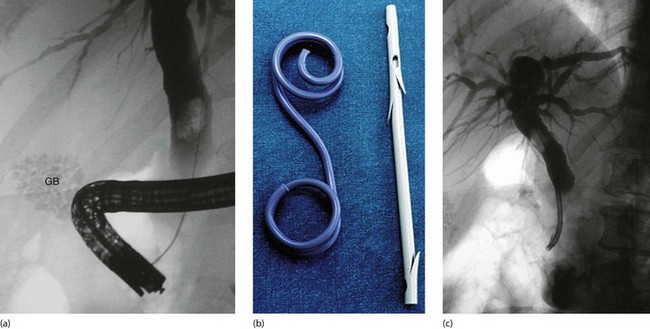

Fig. 18.12 Endoscopic stenting

(a) Diagnostic endoscopic retrograde cholangiogram (ERC) showing an enlarged common bile duct containing a single large stone. A collection of radiopaque gallstones is seen in the gall bladder (GB). (b) Two types of biliary stent: the pigtail type on the left and the notched variety on the right, as used in this patient. (c) Despite endoscopic sphincterotomy, the bile duct stone could not be retrieved so a tubular self-retaining stent has been placed to relieve the obstructive jaundice. The stone was successfully removed endoscopically on a later occasion